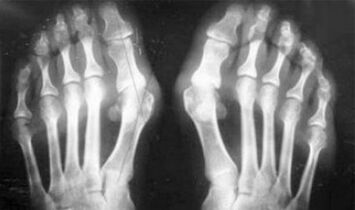

- Violation of the metabolism (gout).

The difference between arthritis and arthrosis of the fingers and hands of the hands is that the first disease healed and the second is not.In arthritis, the synovial bowl and the capsule of the joint are touched.

The cartilage and the bone tissue are defeated only in the late stages in a neglected state.With osteoarthritis, the cartilage tissue is first affected, and then the inflammation of the synovial membrane is a secondary origin, i.e. against its background.